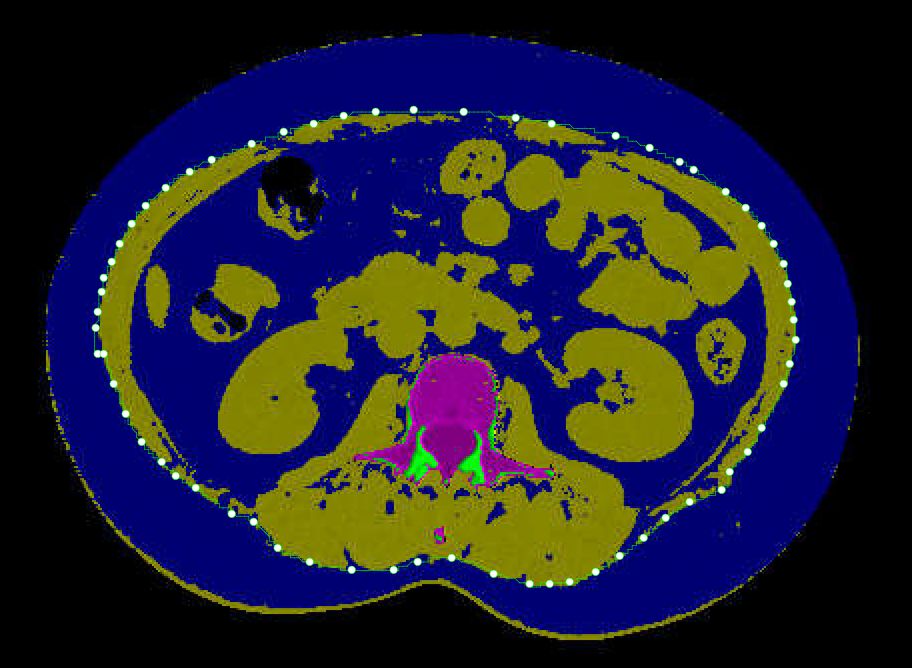

VFA was measured using low-dose chest CT scan data, a routine examination for assessing pulmonary lesions during health check-ups. The scan range included the L3 vertebra, minimizing unnecessary radiation exposure. All participants were scanned using the same 64-detector row CT scanner with standardized parameters: slice thickness 5.0 mm, tube voltage 120 kVp, tube current 100–150 mAs (auto-adjusted based on patient habitus), reconstruction matrix 512×512, calibrated weekly with a phantom (Mindways, Austin, TX, USA) to ensure consistent data quality. After scanning, a trained radiologist measured VFA using the QCT Pro 6.1 supplemental tissue measurement application from Mindways Software. This software performs QCT measurements on two standardized anatomical levels: (1) L2/3 intervertebral space, identified using sagittal reformatted images; (2) umbilicus level, verified by external anatomical landmarks and coronal reformats based on chest CT scan data. The application automatically segmented adipose tissue using standardized Hounsfield unit thresholds (-190 to -30 HU) and calculated the VFA in these slices. The final VFA value represents the average of measurements from both anatomical levels. To minimize measurement errors, care was taken to avoid artifacts from lumbar internal fixation, intestinal gas, or high-density contents. As illustrated in Figure 2. This measurement technique has been validated in the Chinese population (29). Further details on the measurement process can be found in previous studies (30, 31).

Figure 2

Abdominal quantitative computed tomography (QCT) image demonstrates abdominal fat distribution. The dark blue area represents non-adipose tissue and background, yellow regions indicate subcutaneous and visceral fat, and the magenta area represents specific visceral structures. The white dotted line delineates the boundary between subcutaneous and visceral fat compartments.